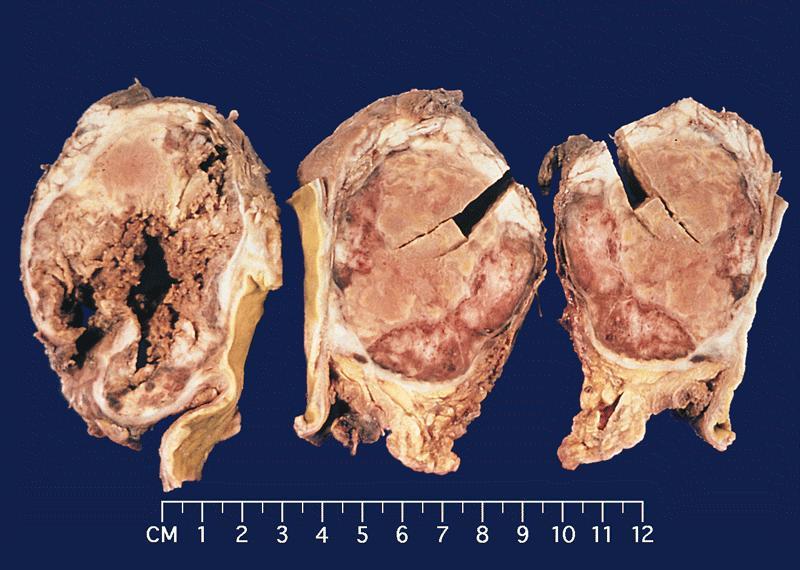

Gross description

- Range from 0.5 to 34.5 cm, with a mean diameter of 6 cm

- Well defined, encapsulated, with variable amount of solid and cystic patterns

- Smaller lesions tend to be more solid but less sharply circumscribed

- Larger tumors demonstrate a fibrous pseudocapsule and have a variegated and friable cut surface

- Cystic degeneration and hemorrhage are common findings in larger specimens

- Rarely, may extend into adjacent structures, such as duodenum

- Reference: Arch Pathol Lab Med 2020;144:829

Gross images

Contributed by Omid Savari, M.D., Dr. Andreas Schulz, Manfred Stolte, M.D., Dr. Helmut Luchtrath, Wei Chen, M.D., Ph.D., Nakul Anush Ravish, M.B.B.S. and Case #121